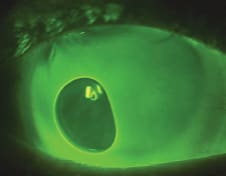

Blanching at the lens edge (Figure 7) is due to a tight peripheral curve or tight landing zone. Blanching can occur at 360 degrees if the curve is too steep, or it can be sectoral if the sclera is asymmetrical. It will often lead to redness after the lens is removed. Blanching requires flattening the edge curve or, for sectoral blanching, can be resolved with toric peripheral curves.

Figure 7. Blanching.